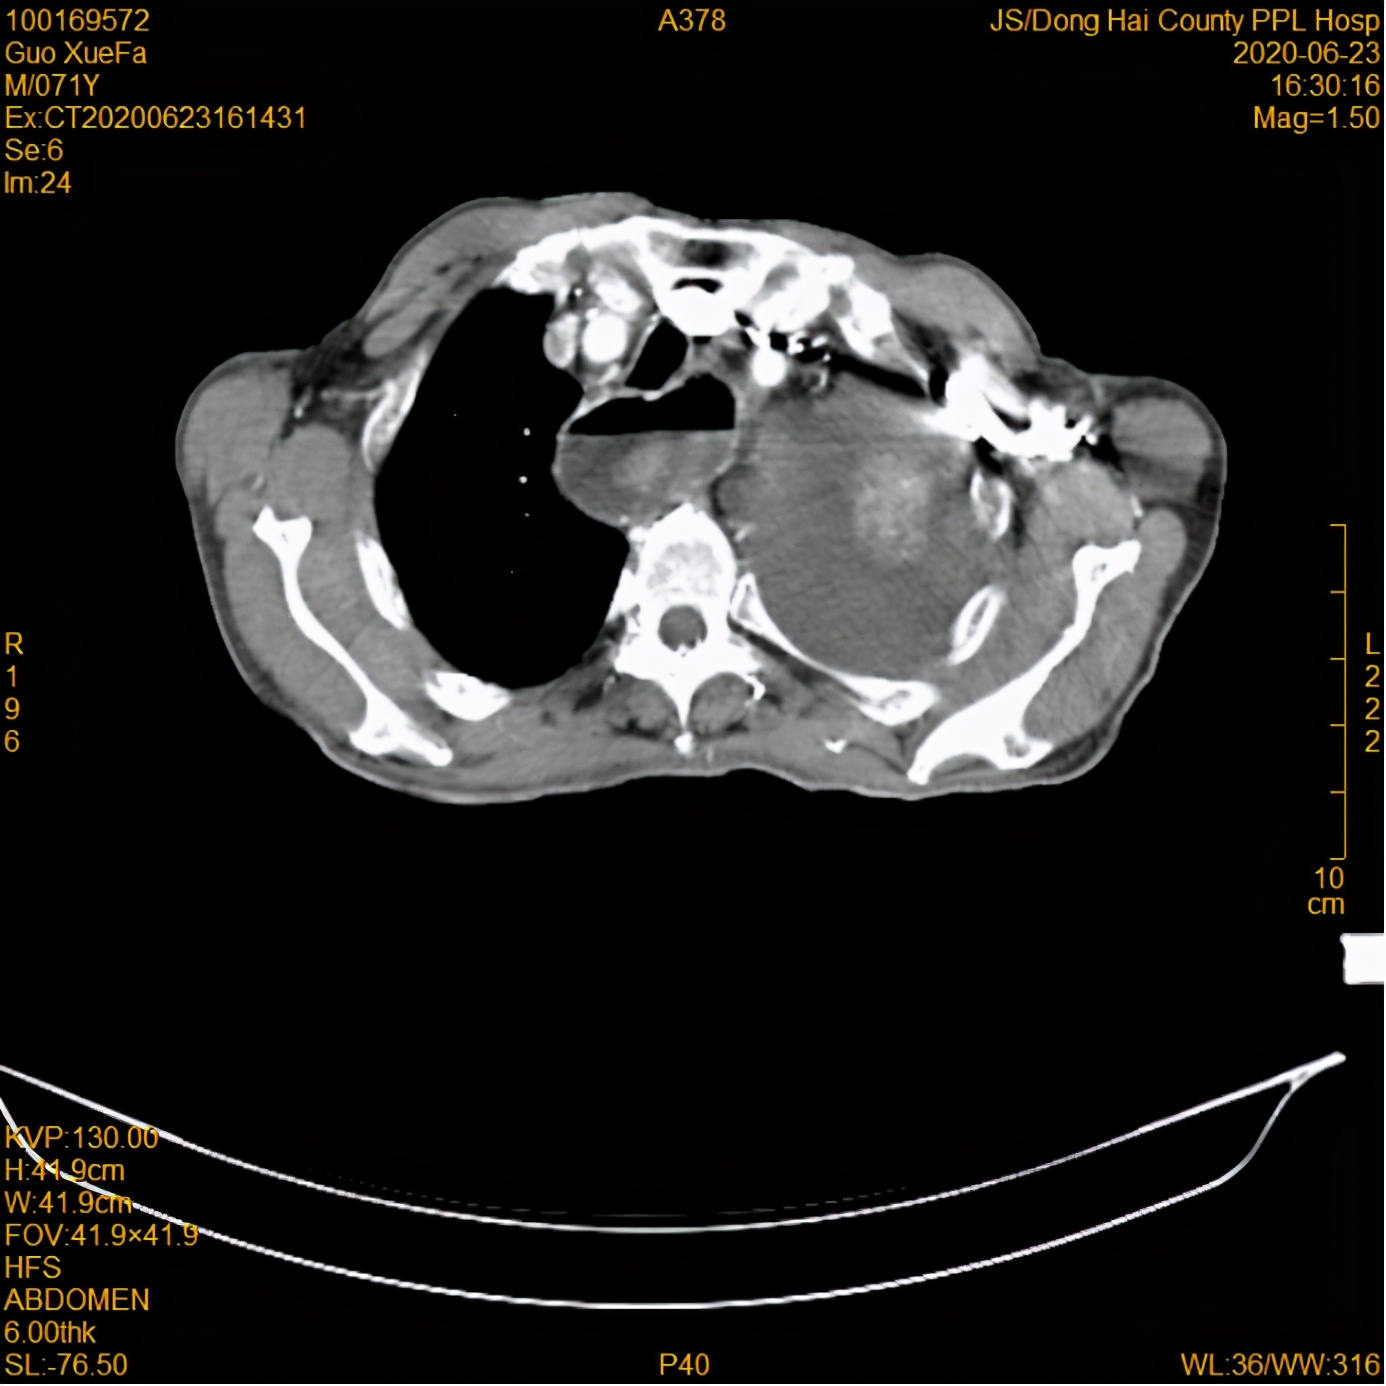

放疗前

16日,郭大爷的女儿带着郭大爷来到我院就诊,经全面检查,郭大爷被确诊为食管癌(伴纵隔、肺门、腹膜后淋巴结转移; 胸腔积液)。